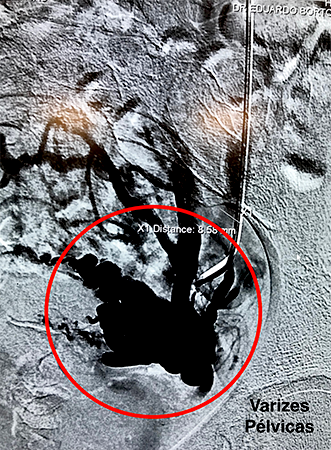

Embolização de Varizes Pélvicas

Varizes Pélvicas é o nome dado para a dilatação das veias localizadas no interior da pelve, próximas ao útero, bexiga e reto. Quando volumosas, essas varizes provocam dor no baixo ventre, dor durante a relação sexual, hemorroidas e varizes na face interna da coxa e períneo. Novas técnicas endovasculares pouco invasivas, permitem o tratamento do problema, com melhora na qualidade de vida desses pacientes.

A embolização de varizes pélvicas é feita através da punção de uma veia superficial do braço. Utilizando cateteres, o cirurgião vascular ocluirá os vasos doentes com liberação de espirais metálicas e substância química na forma de microespuma densa.

As molas em conjunto com a espuma provocarão a oclusão gradual das veias que originam as varizes, levando ao seu desaparecimento.